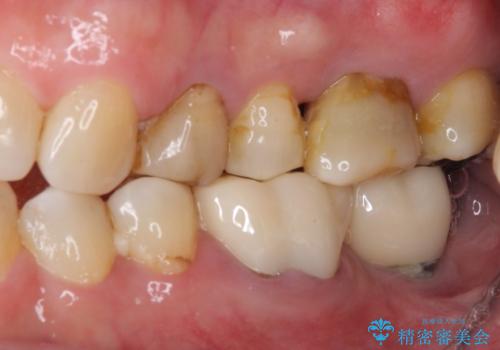

- 60歳を越え、黄ばんだ前歯をセラミッククラウンできれいな口元にしたいとのことで来院された患者様です。

診察したところ、前歯は反対咬合であり、その影響で抜歯が必要な奥歯があることが分かりました。

抜歯が必要な奥歯は、インプラント並びにブリッジにより補綴を行い、上下前歯は反対咬合を改善させるように補綴治療を行うこととしました。

健全な歯を削ってセラミッククラウンに置き換えることは、本来避けるべき治療と考えますが、今回は①患者様が60歳を越えていること、②要改善の咬合により抜歯が必要な奥歯があること、③反対咬合の前歯改善の手段としてセラミック治療が選択肢にあることなどから、全顎的なセラミック治療を行うこととしました。